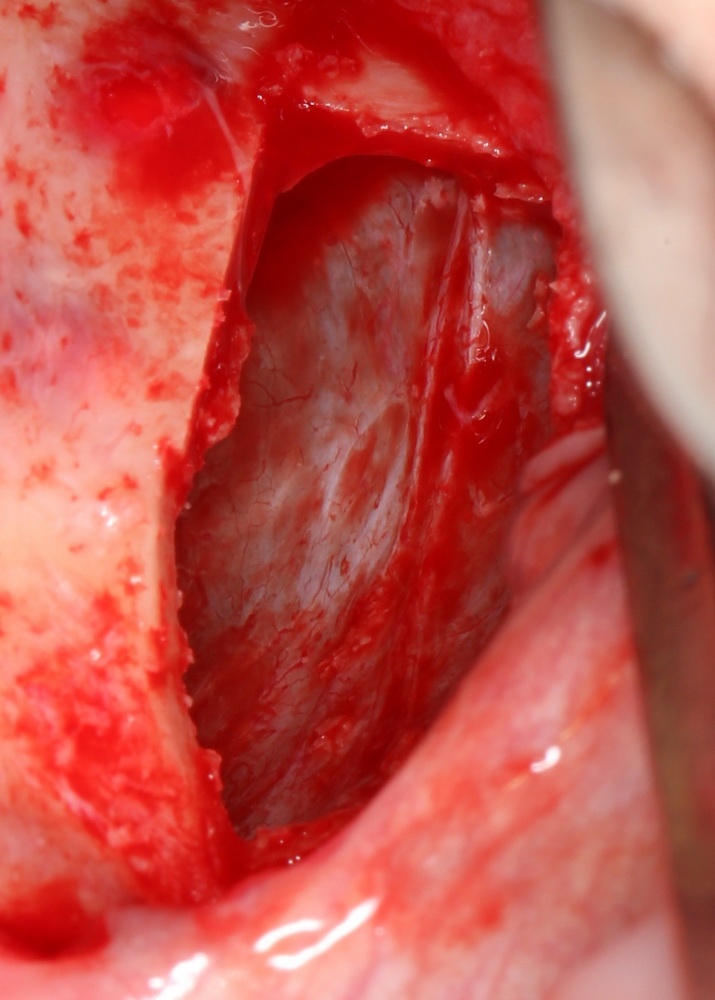

Синуслифтинг: что делать при перфорации слизистой оболочки гайморовой пазухи?